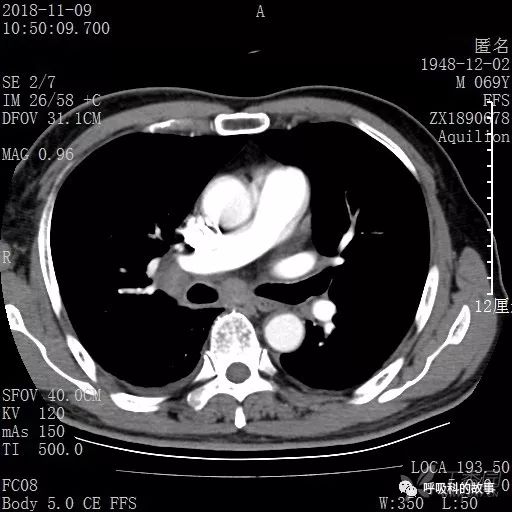

胸部增强CT示右肺门占位伴远端阻塞性肺炎,纵膈、右肺门、右侧颈根部、右侧腋下及肝门部肿大淋巴结。两侧胸腔少量积液。

纵隔窗的增强CT